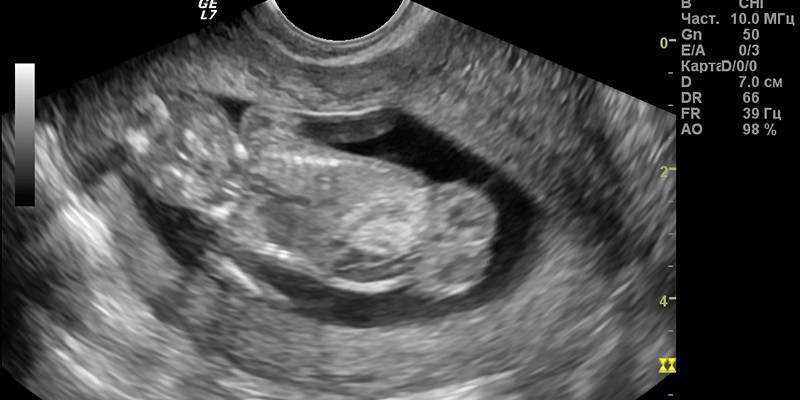

Ближе к концу I триместра форму плода и отдельные части тела видно отчетливо, поэтому с 10-ой недели можно выполнять замеры некоторых зон. Сонологу, проводящему УЗИ скрининг, важно изучить:

- структуру головного мозга;

- копчико-теменной размер и бипариетальный;

- толщину воротникового пространства;

- носовую кость;

- частоту сердечных сокращений;

- длину костей (бедренных, плечевых, голени, предплечья) и парных конечностей;

- размеры сердца;

- число сосудов в пуповине;

- состояние нервной трубки;

- длину от лобной зоны до затылка;

- окружность головы;

- толщину плаценты;

- тонус матки, состояние внутреннего зева ее шейки;

- объем околоплодных вод.